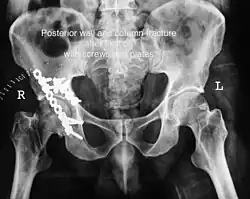

Posterior column and wall fixed using screws and plates